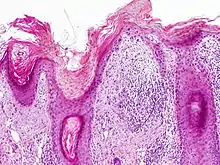

On histologic examination, actinic keratoses usually show a collection of atypical keratinocytes with hyperpigmented or pleomorphic nuclei, extending to the basal layer of the epidermis. A "flag sign" is often described, referring to alternating areas of orthokeratosis and parakeratosis. Epidermal thickening and surrounding areas of sun-damaged skin are often seen.[39] The normal ordered maturation of the keratinocytes is disordered to varying degrees: there may be widening of the intracellular spaces, cytologic atypia such as abnormally large nuclei, and a mild chronic inflammatory infiltrate.[40]

Specific findings depend on the clinical variant and particular lesion characteristics. The seven major histopathologic variants are all characterized by atypical keratinocytic proliferation beginning in the basal layer and confined to the epidermis; they include:[39]

- Hypertrophic: Notable for marked hyperkeratosis, often with evident parakeratosis.[39] Keratinocytes in the stratum malphigii may show a loss of polarity, pleomorphism, and anaplasia.[25] Some irregular downward proliferation into the uppermost dermis may be observed, but does not represent frank invasion.[25]

- Atrophic: With slight hyperkeratosis and overall atrophic changes to the epidermis; the basal layer shows cells with large, hyperchromatic nuclei in close proximity to each other. These cells have been observed to proliferate into the dermis as buds and duct-like structures.[25]

- Lichenoid: Demonstrate a band-like lymphocytic infiltrate in the papillary dermis, directly beneath the dermal-epidermal junction.[39]

- Achantholytic: Intercellular clefts or lacunae in the lowermost epidermal layer that result from anaplastic changes; these produce dyskeratotic cells with disrupted intercellular bridges.

- Bowenoid: This term is controversial and usually refers to full-thickness atypia, microscopically indistinguishable from Bowen's Disease.[25] However most dermatologists and pathologists will use it in reference to tissue samples that are notable for small foci of atypia that involve the full thickness of the epidermis, in the background of a lesion that is otherwise consistent with an AK.[39]

- Epidermolytic: With granular degeneration.[25]

- Pigmented: Show pigmentation in the basal layer of the epidermis, similar to a solar lentigo.[39]